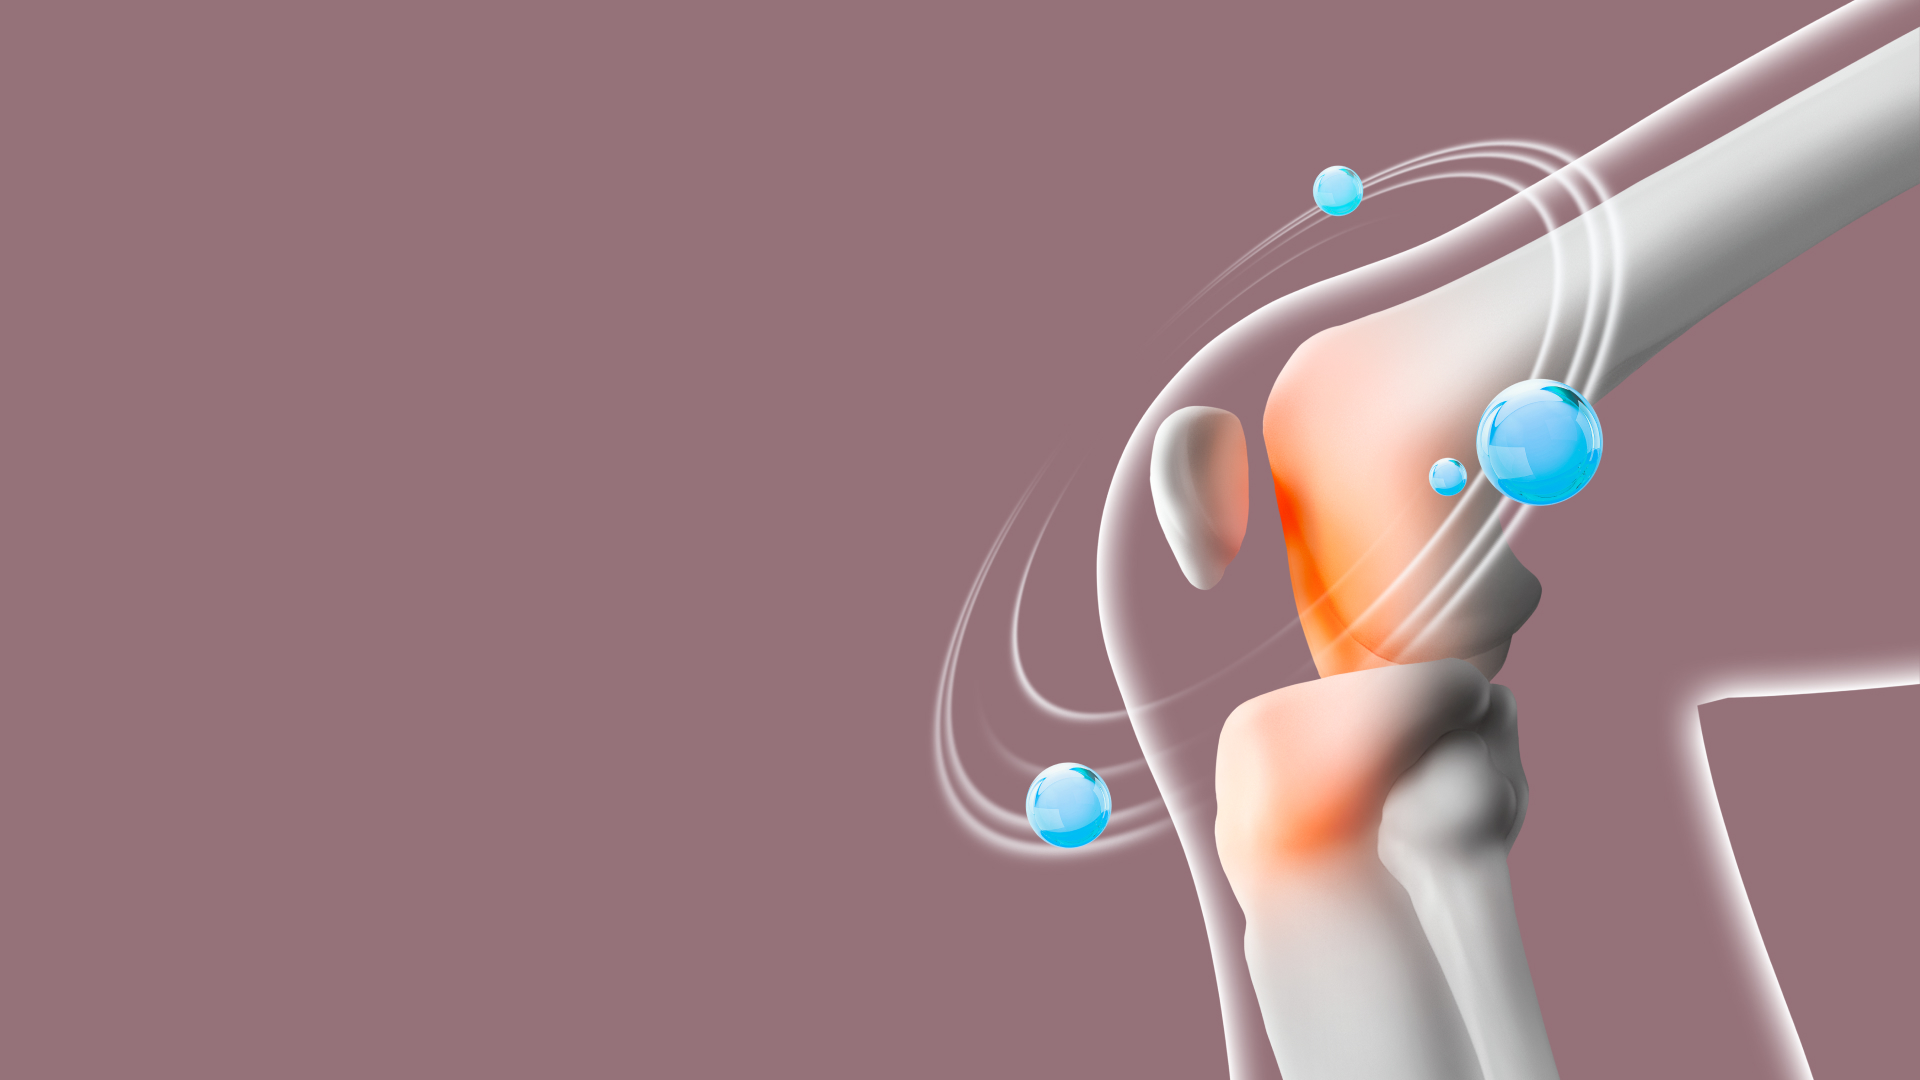

04

힘줄과 뼈의 충돌로 인한 통증

어깨를 많이 사용하는 골프나 헬스, 배드민턴, 테니스 등의 운동을 많이 하는 경우 어깨 부위 힘줄이 어깨 지붕의 뼈와 부딪혀 염증이 생겨 통증이 나타날 수 있습니다.